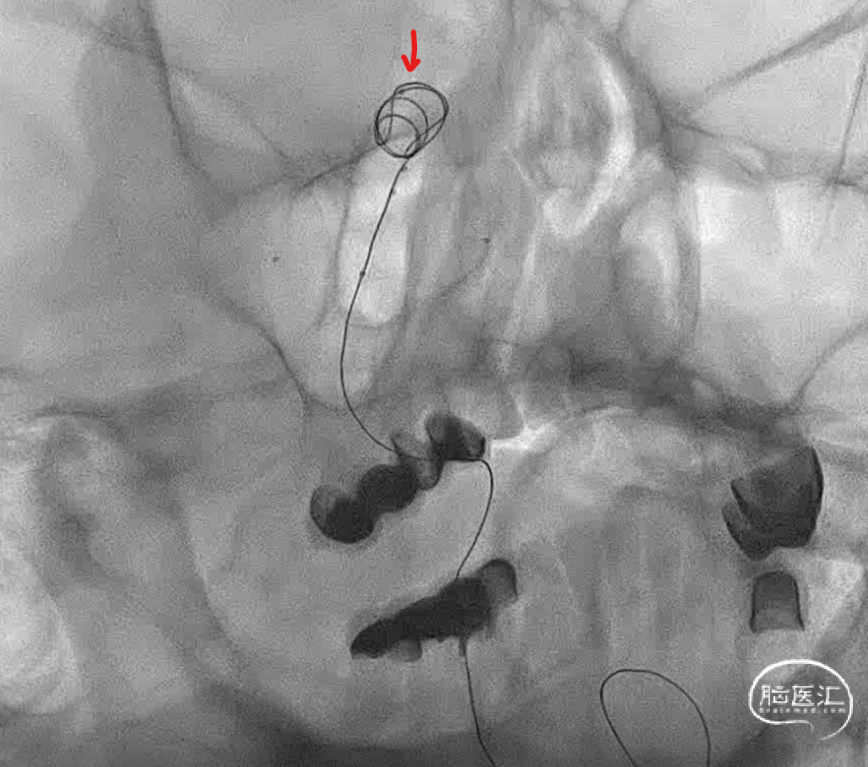

连续填了两枚圈,微导管头没变,但是开始左右摆圈。不好,根据以往经验,瘤顶偏右侧的空间要丢掉机会,如果再填一个圈,即将把动脉瘤颈部偏右侧大脑后动脉部分填致密,这样的话残留在瘤顶部的空白处可能填不上,因此直接采取下一方案。于是趁着瘤颈还有空间,将右侧支架导管撤下,将头塑型为指头或单弯,穿支架网孔到位。

这是微导管到位就放心了,但是一定注意,穿网孔微导管可能有阶梯效应,使其弹射,因此一定要控制好张力,减少戳破动脉瘤的风险。

管他如何,先填个圈把这一部分添上。接下来就是考虑把动脉瘤偏左侧进行正常填塞。

动脉瘤右侧是没事了,但是左侧好像失策了,可以看到左侧部分有一部分圈,但是还是不太致密,但是由于弹簧圈微导管由于在填弹簧圈时,不断减张力,因此已经离开了原来计划的位置。千算万算,好像还是忽略了这一点。